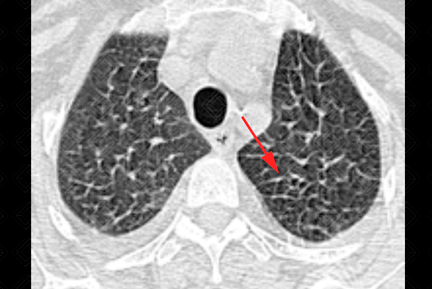

Texto alternativo para a imagem Figura 3. Créditos: Dra. Elazir Mota - Rio de Janeiro/RJ

Descrição das figuras 1, 2 e 3: Tomografia computadorizada de tórax. Espessamento liso dos septos interlobulares (setas vermelhas) associado a discretas áreas em vidro fosco na base pulmonar esquerda (seta preta), moderado derrame pleural bilateral (asterisco azul), derrame pericárdico (asterisco amarelo) e cardiomegalia. O conjunto de achados é sugestivo de congestão pulmonar.

• Tomografia computadorizada de tórax: Opacidades em vidro fosco, espessamento dos septos interlobulares, espessamento peribroncovascular, pavimentação em mosaico, aumento do calibre vascular, consolidações e nódulos de espaço aéreo (como nas figuras acima).